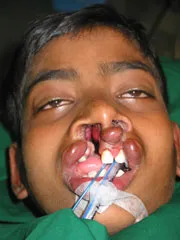

Jaw Cyst with Impacted Teeth

before |

after |